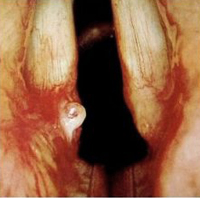

성대폴립

성인의 후두질환 중 가장 흔한 질환으로, 과격한 발성과 흡연이 주된 원인이며 주로 한쪽 성대에 생깁니다. 아스피린과 같은 항응고제의 장기간 사용, 음주, 위산역류에 의한 만성적인 후두 자극, 갑상선기능저하증 등이 원인이 되기도 합니다.

폴립의 겉껍질층의 조직학적 변화는 성대 결절과 큰 차이가 없으며, 증상도 유사합니다.

초기에 치료하면 완전히 회복되는 경우도 있으나 만성화할 경우 염증반응이 지속되어 단단해지므로 수술적 치료의 대상이 되기도 합니다.

보존적 치료로는 음성의 오•남용이나 흡연 등의 원인을 없애고, 초기에는 단기적으로 음성 치료를 시도할 수 있지만, 대부분의 경우에 수술적 치료(후두미세수술)가 필요합니다.